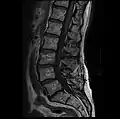

Graphic of lumbar laminectomy and two conditions it can address.

The lamina is a posterior arch of the vertebral bone lying between the spinous process (which juts out in the middle) and the more lateral pedicles and the transverse processes of each vertebra. The pair of laminae, along with the spinous process, make up the posterior wall of the bony spinal canal. Although the literal meaning of laminectomy is 'excision of the lamina', a conventional laminectomy in neurosurgery and orthopedics involves excision of the supraspinous ligament and some or all of the spinous process. Removal of these structures with an open technique requires disconnecting the many muscles of the back attached to them. A laminectomy performed as a minimal spinal surgery procedure is a tissue-preserving surgery that leaves more of the muscle intact and spares the spinal process. Another procedure, called the laminotomy, is the removal of a mid-portion of one lamina and may be done either with a conventional open technique or in a minimalistic fashion with the use of tubular retractors and endoscopes.

The reason for lamina removal is rarely, if ever, because the lamina itself is diseased; rather, it is done to break the continuity of the rigid ring of the spinal canal to allow the soft tissues within the canal to: 1) expand (decompress); 2) change the contour of the vertebral column; or 3) permit access to deeper tissue inside the spinal canal. A laminectomy is also the name of a spinal operation that conventionally includes the removal of one or both lamina, as well as other posterior supporting structures of the vertebral column, including ligaments and additional bone. The actual bone removal may be carried out with a variety of surgical tools, including drills, rongeurs and lasers.

The success rate of a laminectomy depends on the specific reason for the operation, as well as proper patient selection and the surgeon's technical ability. The first laminectomy was performed in 1887 by Victor Alexander Haden Horsley,[2] a professor of surgery at University College London. A laminectomy can treat severe spinal stenosis by relieving pressure on the spinal cord or nerve roots, provide access to a tumor or other mass lying in or around the spinal cord, or help in tailoring the contour of the vertebral column to correct a spinal deformity such as kyphosis. A common type of laminectomy is performed to permit the removal or reshaping of a spinal disc as part of a lumbar discectomy. This is a treatment for a herniated, bulging, or degenerated disc.